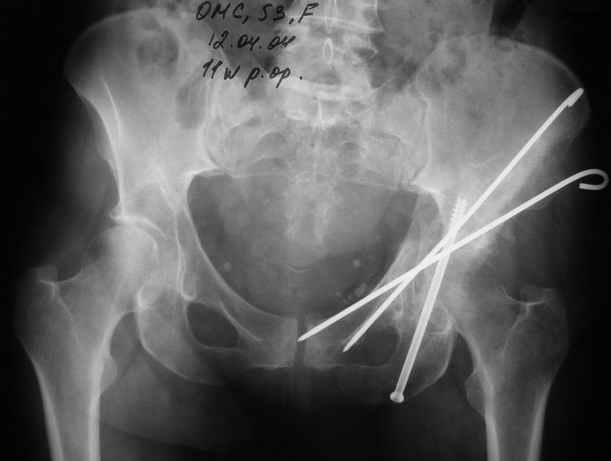

12.04.04

Надо сказать, что сочетание переломов вертлужной впадины + шейка + диафиз бедра - довольно редкое. Шейка+диафиз - 5% от переломов бедра, впадина + шейка = 5% от переломов впадины, а уж все три перелома...

Что интересно, при переломах шейки и диафиза бедра перелом шейки всегда с вертикальной линией. То есть фиксировать надо хорошо, и лучше с вальгизацией. Поэтому вполне приемлем и ретроградный остеосинтез диафиза бедра, а шейки - отдельно спонгиозными винтами. Если необходима операция на вертлужной впадине с отсечением большого вертела, это, наверно, наиболее практичный вариант.